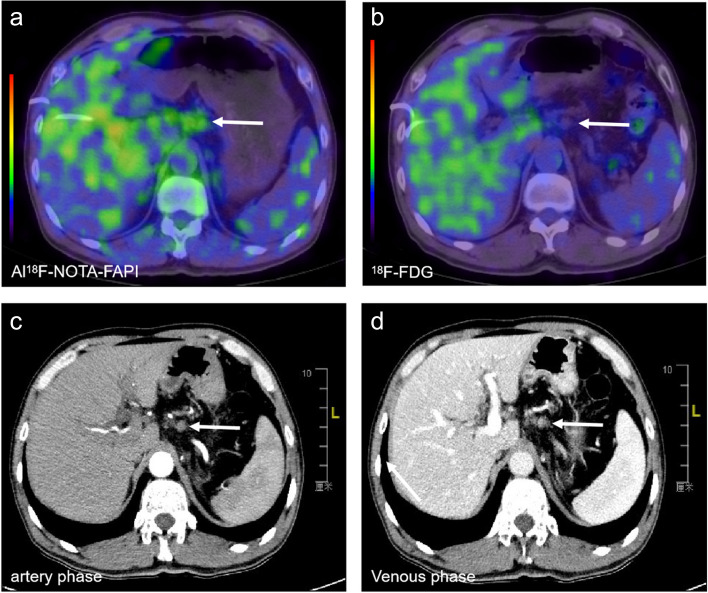

Changes in TNM staging after Al18F-NOTA-FAPI-04 PET/CT and clinical management

Compared to 18F-FDG PET/CT, Al18F-NOTA-FAPI-04 PET/CT improved the N stage in 16/31 patients (51.6%). A total of 16 patients had their TNM staging upstaged as a result of the new lesions detected by Al18F-NOTA-FAPI-04 PET/CT, and all changes are up-staging (Table 2). Seven cases (22.6%) were upstaged by detecting Al18F-NOTA-FAPI-04 uptake in abdominal lymph nodes, leading to an upstaging to stage IIB (Fig. 5A-D), and nine cases (29.0%) were upstaged to stage III. Because of newly detected lymph node metastases, the therapeutic regimen was changed in 12 patients (38.7%, surgically resectable to unresectable).

Fig. 5.

An evaluation of a patient with a local PDAC. Al18F-NOTA-FAPI-04 PET/CT showed increased FAPI uptake in lymph nodes (a, white arrow, SUVmax-15min=4.8), which all showed no uptake in 18F-FDG PET/CT (b, white arrow). Meanwhile, the contrast-enhanced CT showed little enhancement in both arteries (c, white arrow) or the venous phase (d, white arrow). Thus, the N stage was upstaging to the IIB